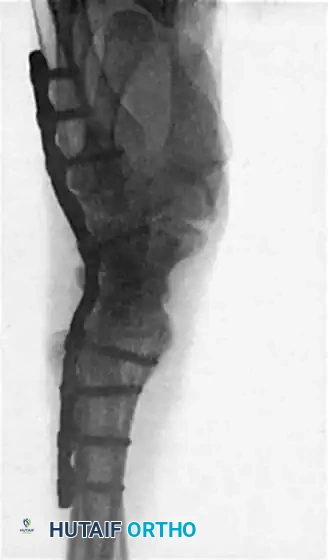

5. Radiographic Confirmation and Closure

• Obtain intraoperative fluoroscopy (AP and Lateral views) to confirm hardware placement, screw length, and joint compression. Ensure the plate holds the wrist in the optimal 10 to 15 degrees of extension.

Image